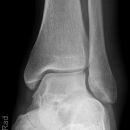

Sprunggelenk

Weber A

Es wurden keine Bilder gefunden.

Weber B

Weber C + dorsales Volkmann

Trimalleoläre

Vorderes Volkmann + lat. Talusschulter